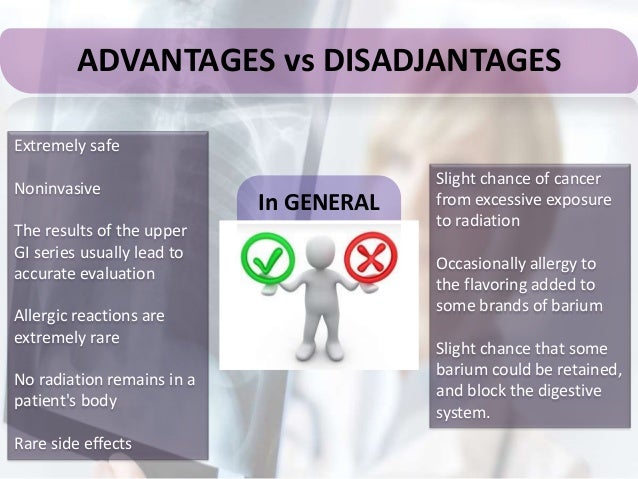

Advantages. Done without sedation. Very low risk. Less expensive than a colonoscopy. Identifies lesions in the entire colon. Accurate for finding abnormalities, such as narrowed areas or pockets or sacs, in the intestinal wall. Can find cancer in earliest stage, when most treatable. Slight risk of perforation.

What are the advantages and disadvantages of DCBE?

The advantages of DCBE is that it provides screening for the whole colon and is relatively safe, with a perforation rate of 1 in 25,000 and an associated mortality rate of 1 in 250,000, 68 compared with 1 in 1000 patients undergoing colonoscopy. 69 The disadvantages of DCBE include need for rigorous bowel preparation, discomfort during the procedure, and operator and reader dependency on interpretation of results.

Advantages

Disadvantages

- Polyps cannot be removed during the procedure — you will need to get a colonoscopy if abnormalities are spotted on X-rays

- Requires laxative preparation

- Some may find the test uncomfortable

- Availability is decreasing; usually only for those who cannot undergo colonoscopy